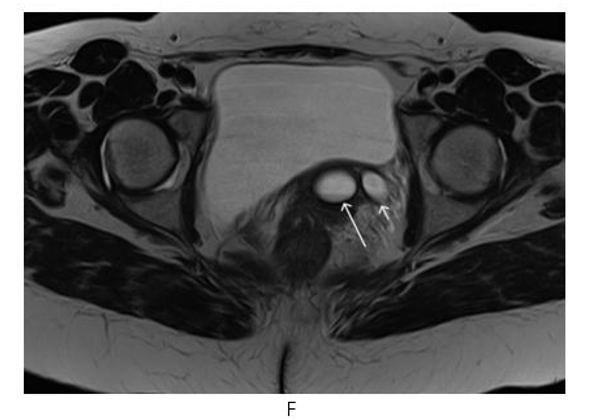

Figure 7: Pelvic MR Non-Enhanced Coronal STIR (G) Image: Gartner’s Duct Cyst (Short Thin Arrow), Urinary Bladder (Long Thick Arrow), Tubular structure (Short Thick Arrow), Tubular Structure Opening into Gartner’s Duct Cyst (Long thin Arrow)